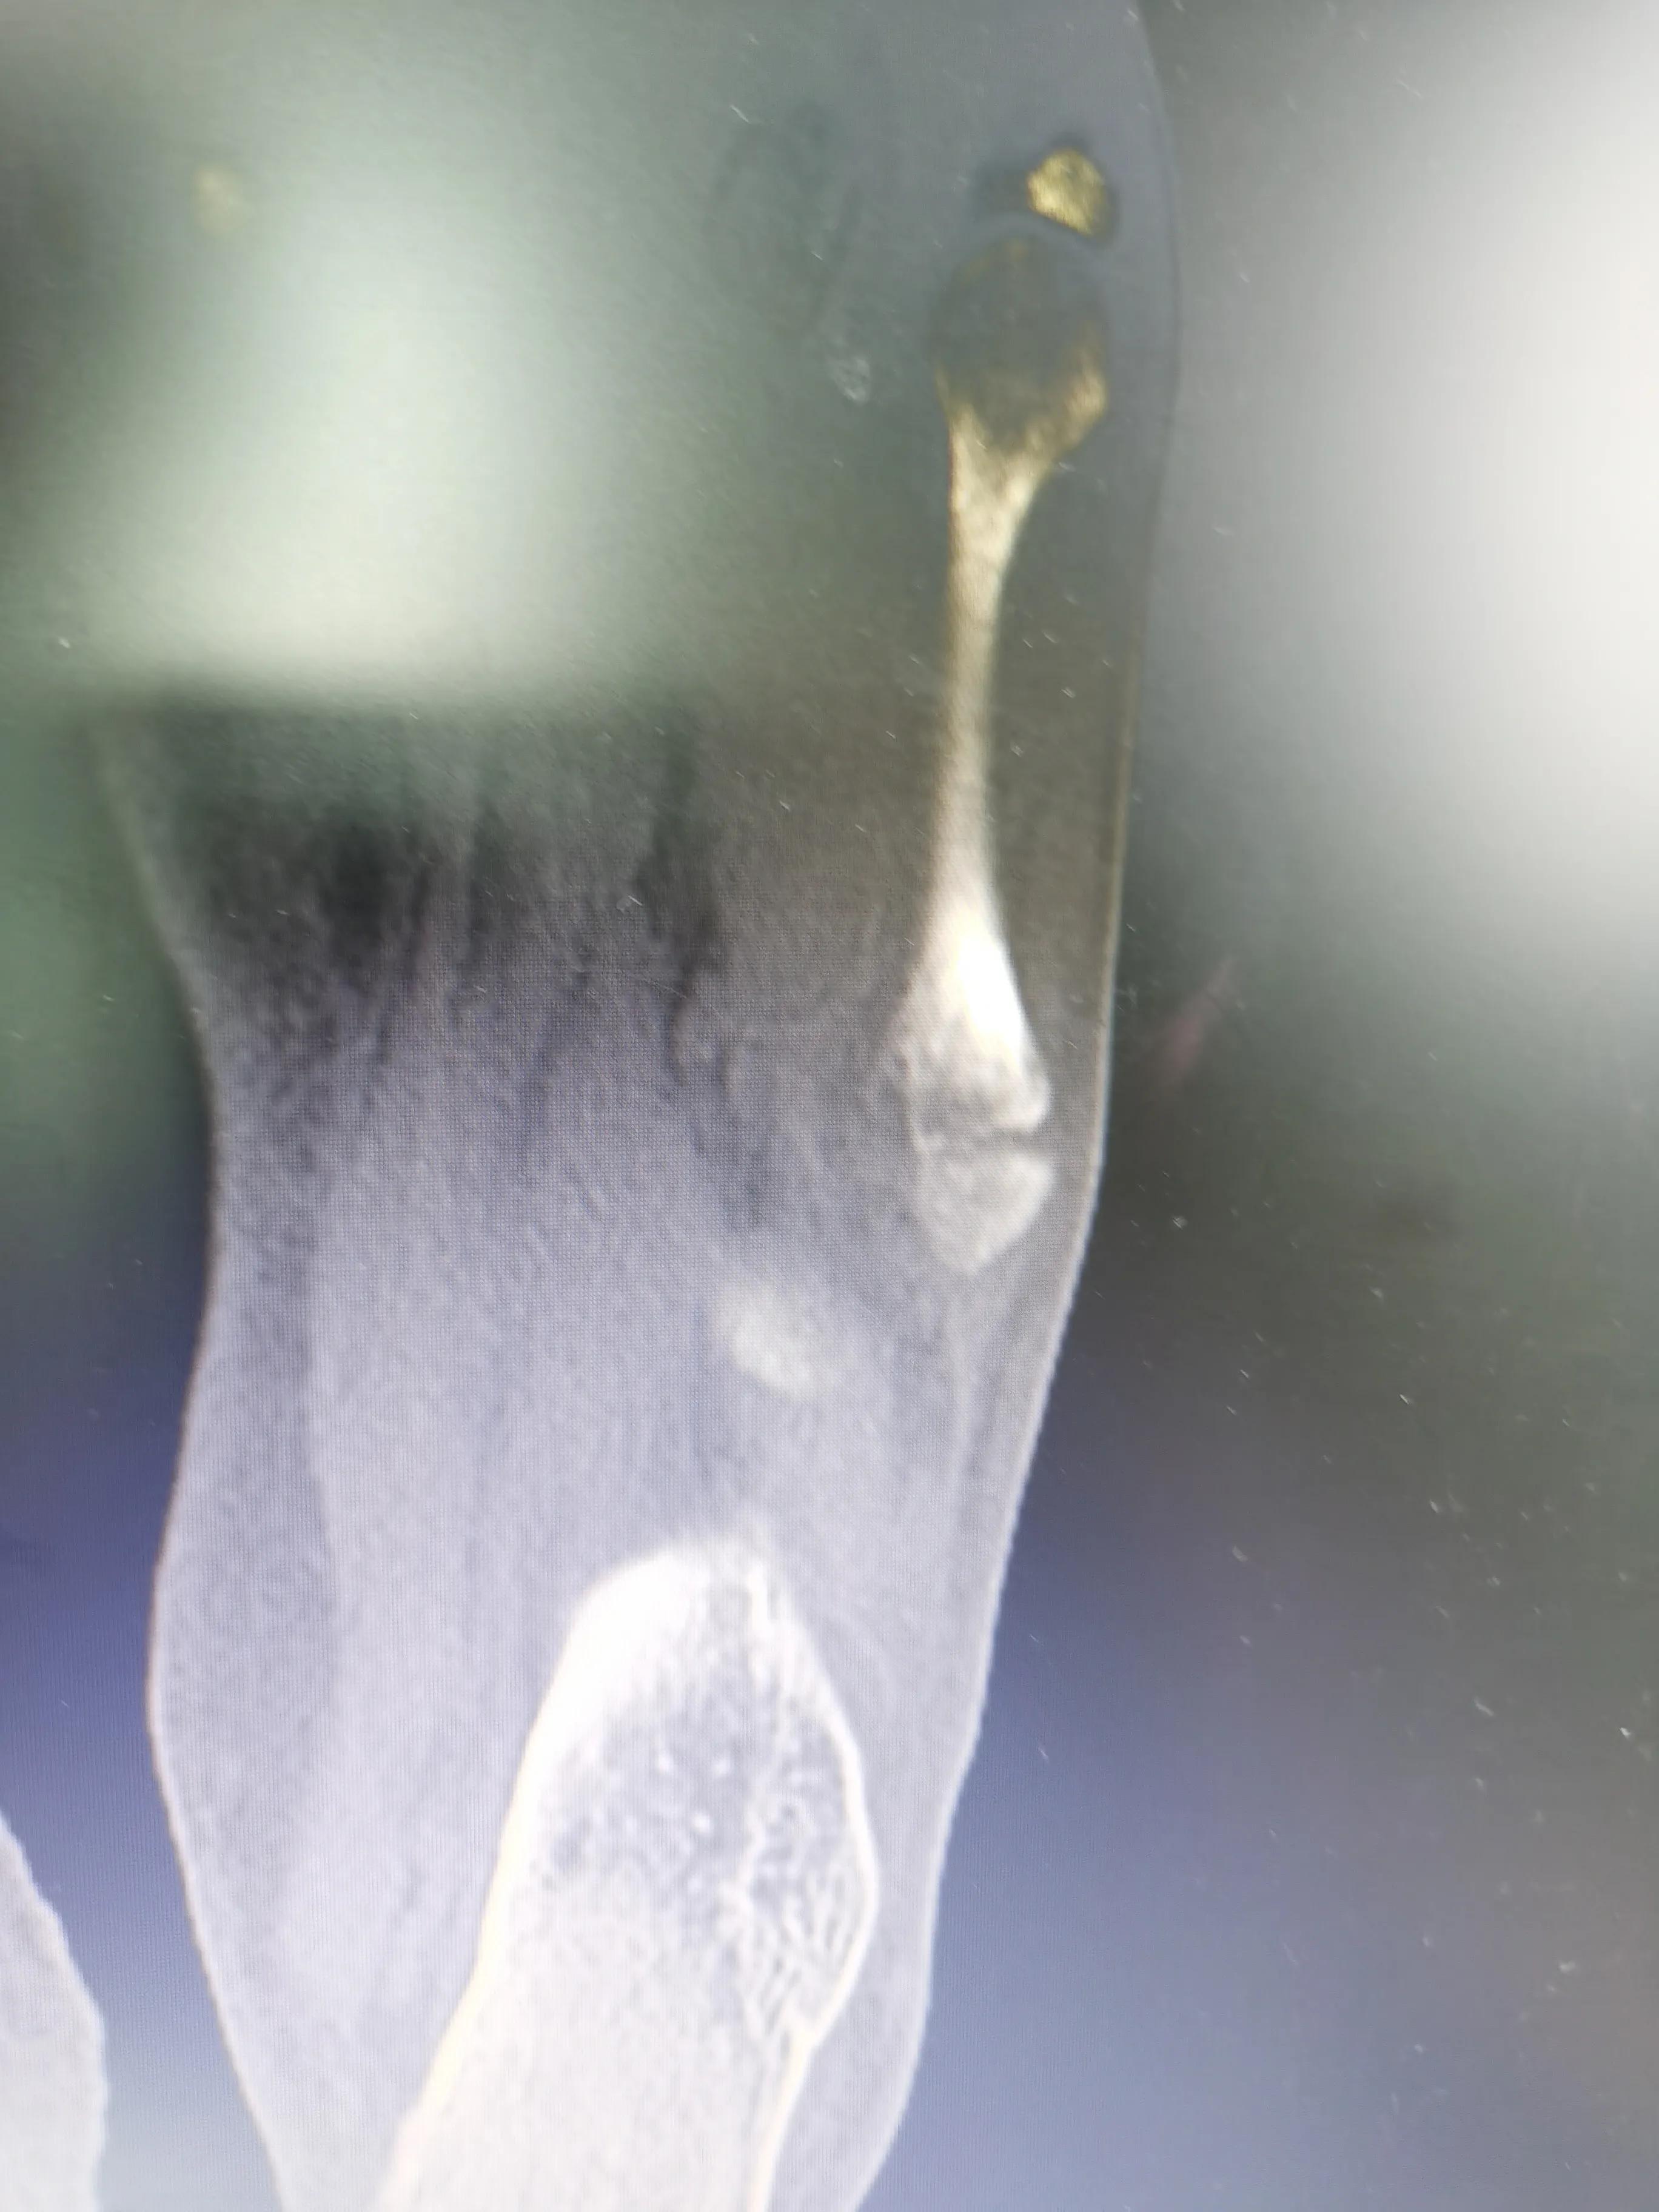

这是CT诊断书

看片子骨缝比较大了,有点移位,而且中间崩碎了一块,一直找不到,后来复查才发现那个碎片掉落在骨缝当中了

此图可以看见中间碎片在骨缝里面